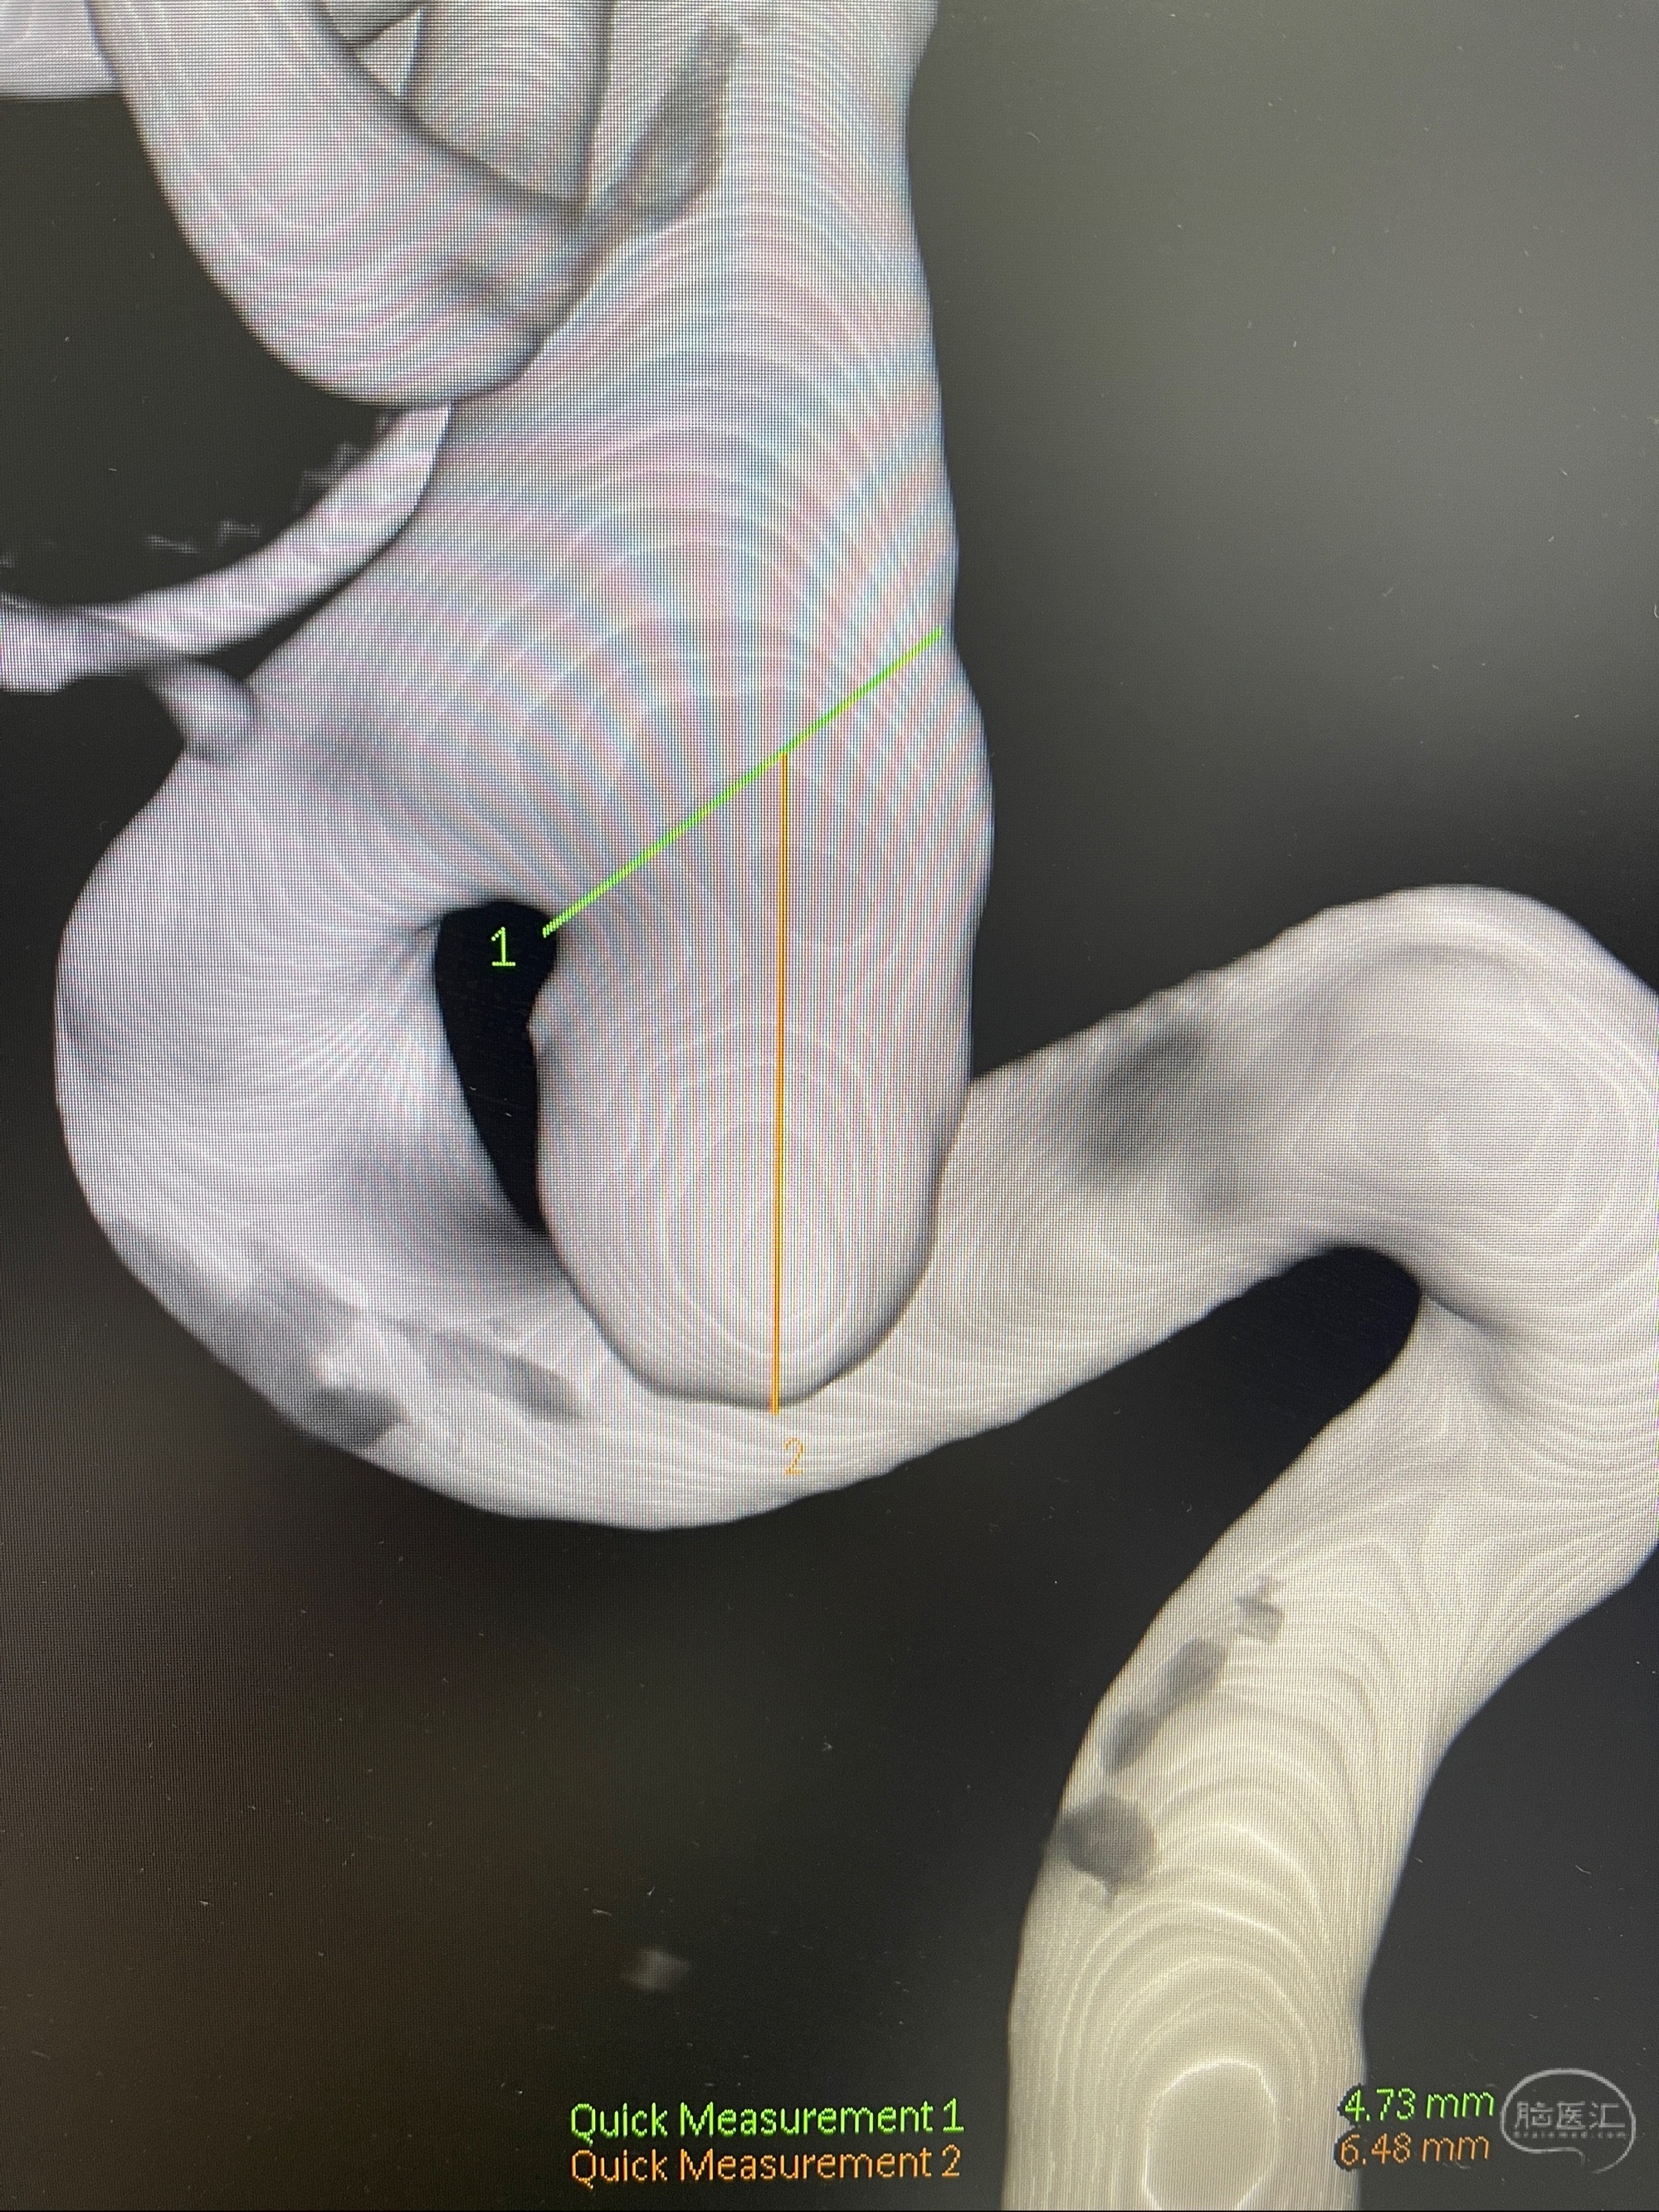

1.右侧颈内动脉眼动脉段动脉瘤

CTA示:右侧颈内动脉C6段见指向下方的突起,余左侧颈内动脉、双侧椎动脉、大脑前动脉、大脑中动脉、大脑后动脉及基底动脉走形正常,未见明显扩张及狭窄,局部未见明显瘤样扩张。

2023-07-27全脑血管造影:双侧颈内动脉眼动脉段动脉瘤,右侧较大

2023-08-01全麻下行双侧颈眼动脉瘤支架辅助栓塞

- pipeling4.5-20mm

- pipeline 4.0-20mm